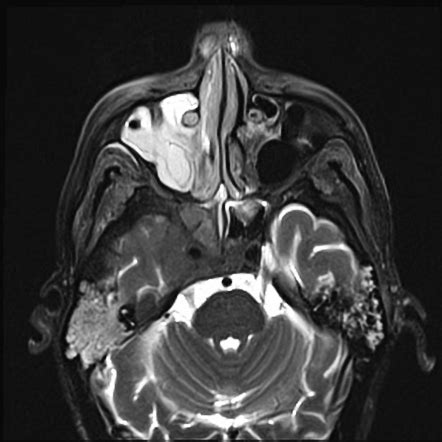

Learn about Cavernous Sinus Syndrome, a serious medical condition affecting critical cranial nerves. Discover the primary symptoms, such as ophthalmoplegia and vision loss, alongside common causes like cavernous sinus thrombosis or aneurysms. Understanding these neurological warning signs is vital for timely diagnosis, effective clinical management, and improving patient outcomes. Get the essential facts on this complex intracranial disorder today.